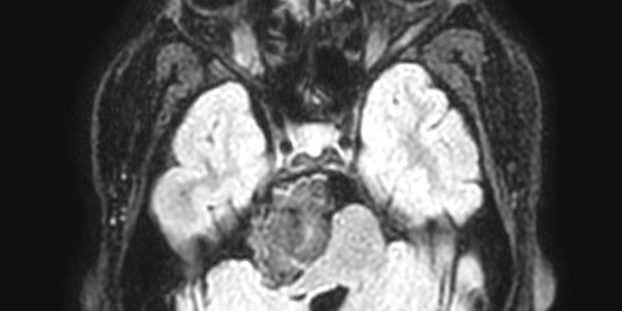

Ασθενής 19 ετών με γνωστή χωροκατακτητική εξεργασία (επιδερμοειδες γεφυροπαρεγκεφαλιδικής γωνίας δεξιά) με προοδευτικά σημαντική αύξηση μεγέθους. Νευρολογικά ακέραιος.

Ο απεικονιστικός έλεγχος με μαγνητική τομογραφία ανέδειξε ευμεγέθη εξεργασία στη δεξιά γεφυροπαρεγκεφαλιδική γωνία.